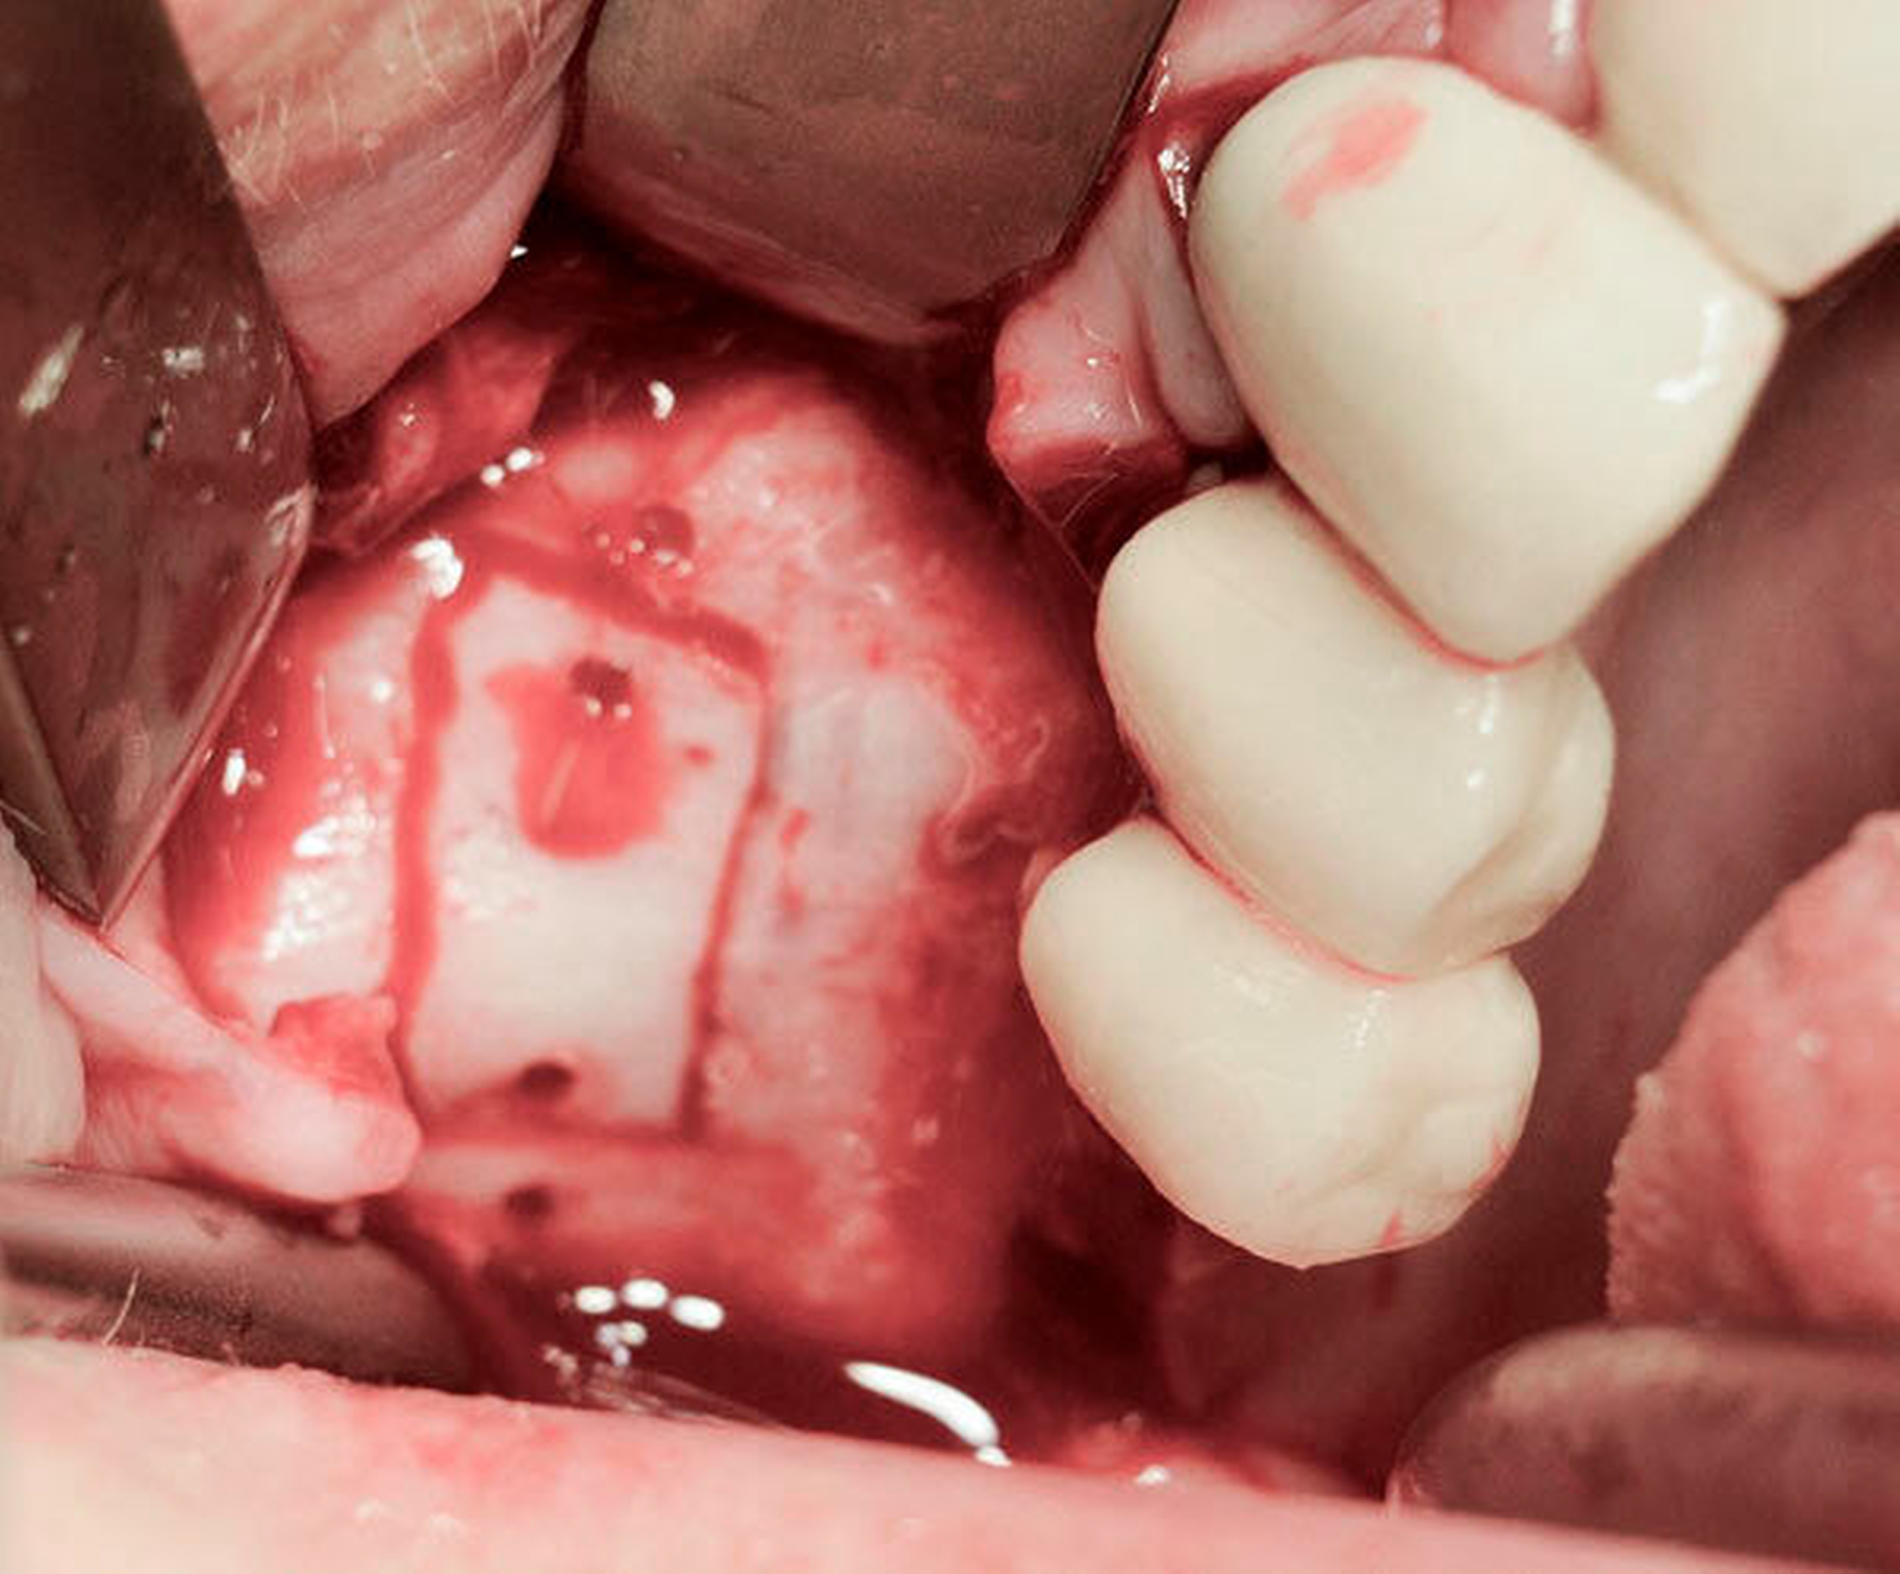

Eine röntgenologische Routineuntersuchung ihres Zahnarztes ergab im April 2017 die vollständige Luxation des Implantats 17 in die Kieferhöhle direkt aus der prothetischen Versorgung heraus (Abbildung 3). Die Patientin hatte ebenfalls keine klinischen Beschwerden.

Im Fall des luxierten Implantats wurde in Intubationsnarkose ein Knochendeckel angelegt (Abbildung 8) und das Implantat über diesen Zugang extrahiert (Abbildungen 9 und 10).

Klinisch zeigten sich ausgeprägte polypöse Schleimhautveränderungen. Die ehemalige Insertionsstelle des Implantats war vollständig verschlossen. Nach Entfernung des Implantats, Reposition und Fixation des Knochendeckels wurde der Mukoperiostlappen in Ursprungsposition vernäht.